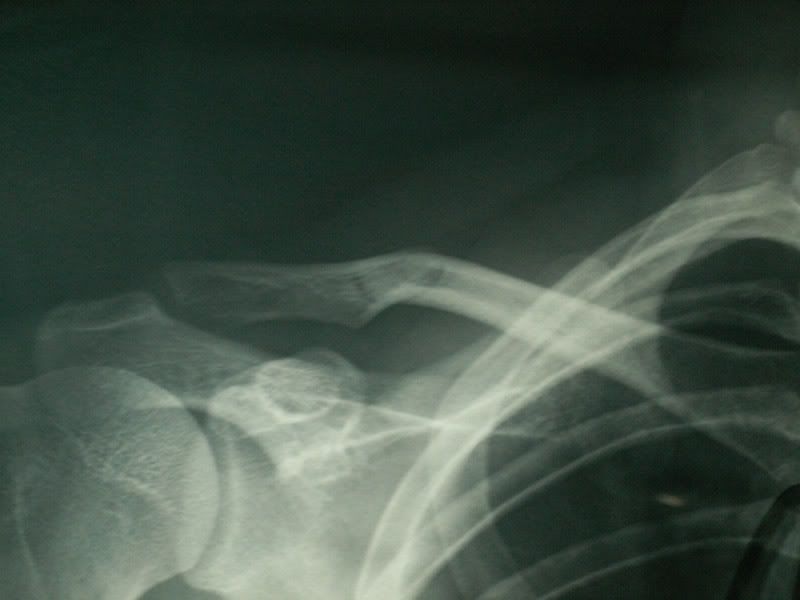

骨折没移位,当时的处理没错了,最好有另外一边的x片对比一下,不过我估计都好了,是吗?

貌似是锁骨骨折。。

是锁骨弯曲...还没断哈...